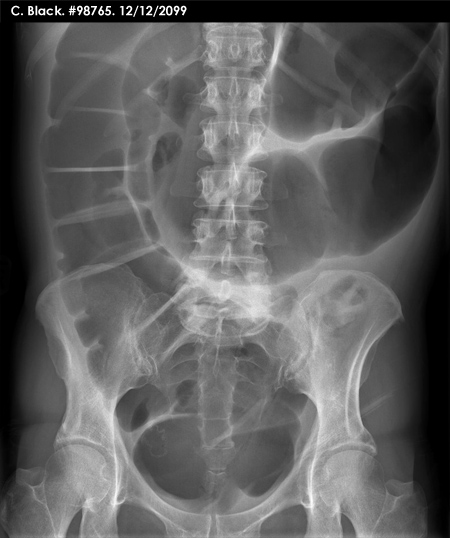

Abdominal X-ray - Scenario 3

- Take a moment to view the image

- State your summary clearly before clicking the 'Next' button

- Which other X-ray would you like to see in this clinical setting?